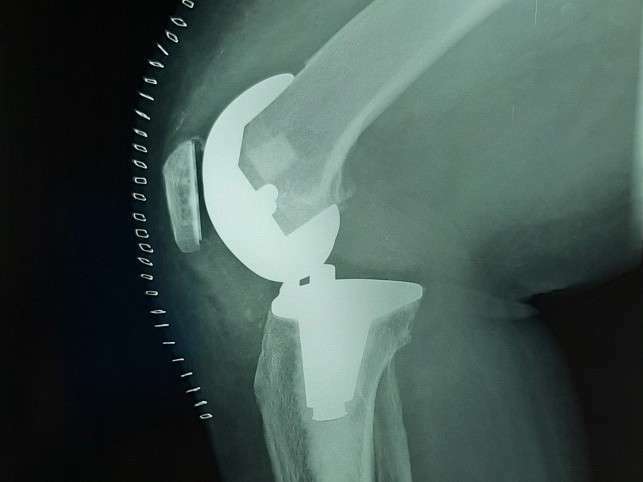

Cas 1. Luxation fémoro-acétabulaire de PTH

Cas 2. Luxation intra-prothétique de PTH